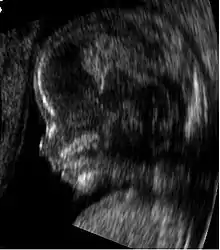

Embryon à 8 semaines

L'embryon mesure entre 15 et 22 mm. La vésicule vitelline qui le nourrit est juste à côté. À la fin de cette semaine, les coudes deviennent visibles